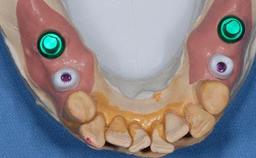

Bone Augmentation Simultaneous

Augmentation Materials Xenogenous

Abutment Type Customized